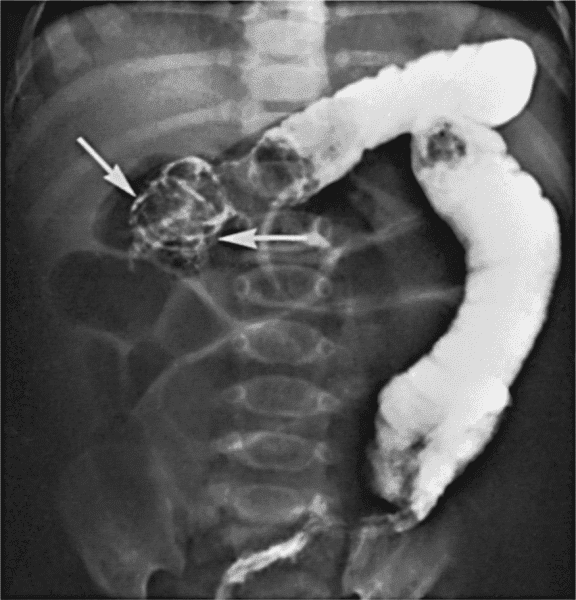

Hirschsprung Hastalığı Belirtileri

Hirschsprung Hastalığı Nedir? Hirschsprung hastalığı; kalın bağırsaklarda hareket bozukluğu nedeniyle ortaya çıkan tıkanıklıktır. Bu hastalık...